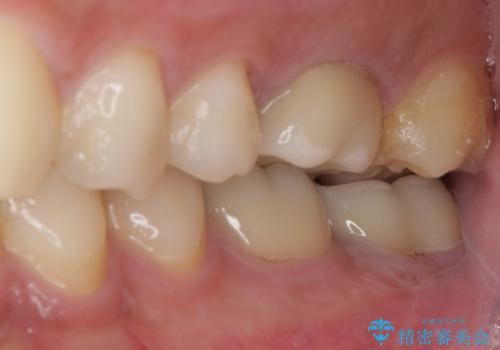

- 間もなく海外赴任という状況で奥歯のクラウンが割れてしまったとのことで来院された患者様です。

下顎の1番奥の歯であり、歯肉に覆われている部分が大きいためセラミックの十分な厚みが取れない状態でした。

強化セラミックを用いたオールセラミッククラウンにて補綴治療を行うこととしました。